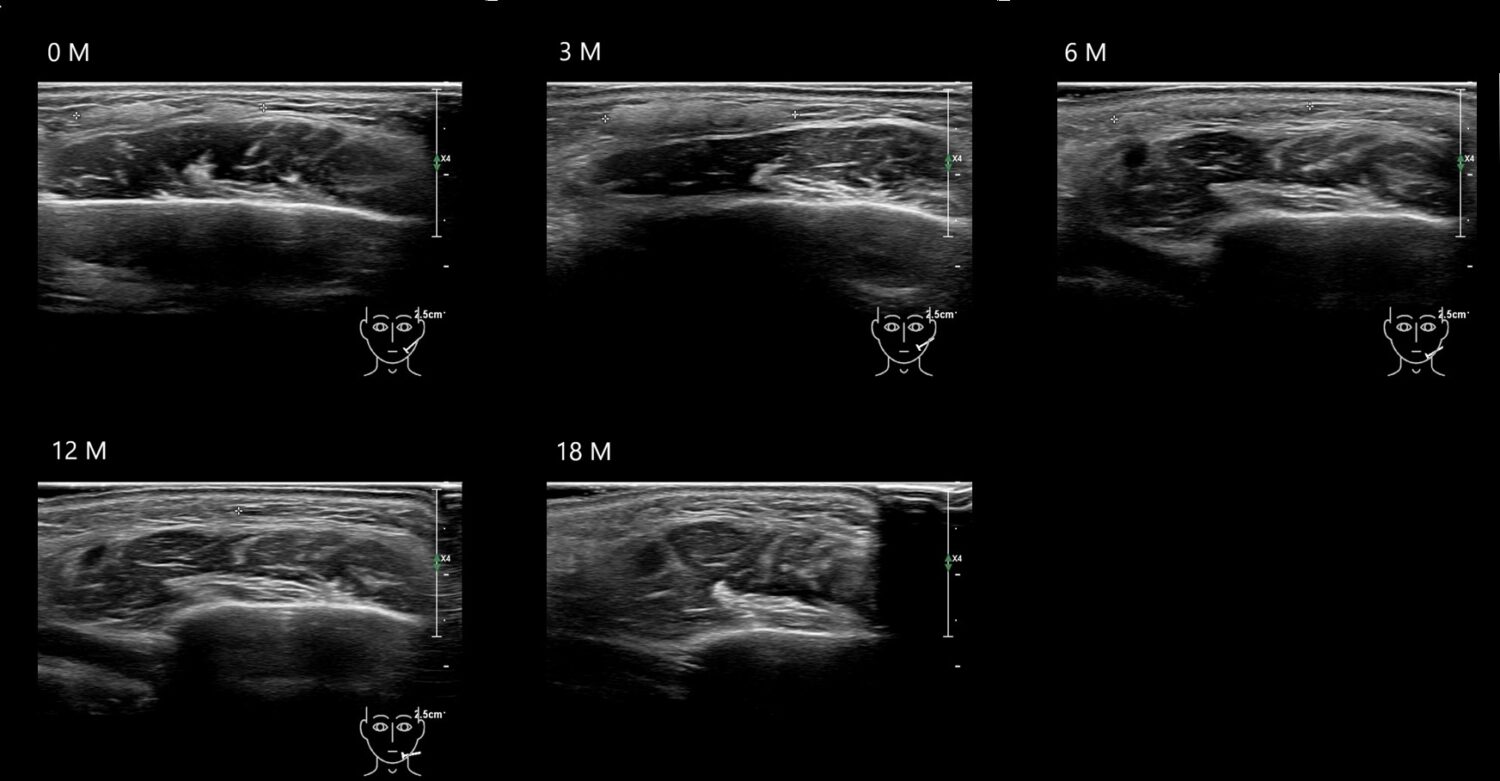

Filler library